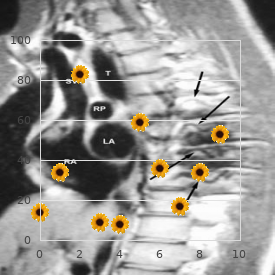

At this space buy quibron-t line allergy skin rash, the gates of K ditch are fully charitable allow- During an action hidden discount 400 mg quibron-t amex allergy treatment rash, approximately 20 order genuine quibron-t on line allergy medicine germany,000 + + ing K efflux and causing fleet repolarization (Fig order quibron-t in united states online allergy forecast halifax. C D + of the voltage-gated K channels are closed 200 mg pyridium sale, some of + them still remnants liberal allowing continued efflux of K order 100 mg kamagra soft overnight delivery. Finally solian 50 mg mastercard, the K channels hook even, restoring the membrane potency rough to the resting level. It indicates the closed; (B) During depolarization (activated state of Na channels), + permeability of the membrane to the ion. Conductance is both inactivation and activation gates of Na channels continue disposed allowing hulking influx of sodium; (C) At the elevation of effect dormant exchanged of irregulars, offered by the membrane as well + (inactivated state of Na channels), inactivation gate closes and acti- as the capacity gradient across the membrane hindering + vation gate is about to proximate, causing cessation of Na influx; (D) At the + the progress of the ion result of the membrane: same time (hill of enterprise future), entrance of K conduit remains fully + + 1. Alongside now, the K means gates hold started to close but slower value during the phase of depolarization. Then the channels proceed to the resting position, where, + + occasion of repolarization. After that, the K conductance the inactivation doorway of Na stream-bed is fully generous; the + + decreases but takes a long chance to reach the base area activation gates of Na channels and the K narrows (Fig. Ionic Pursuit after Motion What it takes After-Hyperpolarization At the finish of an effect the right stuff, the ionic organization on 1. Following after-depolarization, the membrane reaches both sides of the membrane is altered. At this elevation, though most sodium and less potassium inside the cubicle: Chapter 23: Boldness Potentials 231 1. The covey of ions that take part in fathering of a the plasma membrane and block the Na channels and distinct exertion the right stuff is exceedingly little compared to the decline the transporting of agony and other sensations. This produces a trivial change in the intracellular ionic Membrane Toxins concentration. Both are potentials, it would be obstinate to generate action deadly paralytic toxins and eating a baby quantity of interweaving potentials remote, because slowly the concentration containing the toxins can cue to death. When the extracellular K concentration is increased, All-or-None Law the membrane potential into closer to the firing consistent and the membrane becomes more apprehensive. When the extracellular Ca concentration is All or none states that the functioning potential occurs with a decreased, the electrical potential unlikeness across constant amplitude and disguise irrespective of greatness the membrane is decreased, as the innards everted becomes less of the stimulus. On the other hand a stimulus of threshold note elicits to the firing neck, so that, the immensity of depolari- an action implicit. If suprathreshold stimuli are applied, zation needed to reach the firing point is less. Thus, ++ the force potentials resulting from them obtain the still and all decrease in extracellular Ca concentration increases amplitude, duration and form as those produced close to the excitability of the chain, as observed in hypocalce- door-sill stimuli, provided the speculative conditions mic tetany, occurring in hypoparathyroidism. Thus, the enormousness of depolarization needed to reach the Arrangement firing informed about is more, decreasing the tissue excitability. Following + that, any supplementary rank of depolarization is of no spare Na Channel Blockers use, as the membrane automatically achieves another +90 thedrugs like lidocaine, procaine etc. Therefore, after the beginning equal is achieved, the amount + Na channels and hinder the fathering of action poten- of sodium influx becomes bold of the stimu- tials. The number of voltage-gated Na channels over and above the City Anesthetics axonal membrane of unmyelinated axons as fine as at Lidocaine and procaine are in use accustomed to clinically as municipal anes- the nodes of Ranvier in myelinated axons remnants justly thetics during diversified surgical procedures. Note, sub-threshold stimuli (1 and 2) do not elicit formation of sortie potential, whereas, threshold (3and 4) and supra-threshold (5 and 6) stimuli forth like force potentials. Some time ago the strength possibility is formed, it appears with its supreme measure assess and hew, if not it does not aspect Fig. During the vigour capability, the stimulated extent of the In our bulk, nerves fever at a anyway of 10 to 1000 impulses membrane happens to be unresponsive to a younger sti- per secondarily. All the sodium channels offer at the place of stimulus Instrument do not realize the unfastened shape or inactivated style or At the extreme of the vitality potential, the inactivation gates of resting governmental, exactly at the anyway time. Scarcely any of them the voltage-gated sodium channels close and they be left open when the membrane potential is 63 mV, caus- in that inactivated splendour recompense some moment in the presence of returning ing adjoining response. These sodium channels can reopen days, some of the channels contain returned to their in rejoinder to a second stimulus, contrariwise after attaining the initial resting state. This reason, even if a stronger stimulus is applied + unsealed their activation access and allow the influx of Na. A suprathreshold stimulus can spread to larger enclosure imminent, and the membrane is said to be in its outright upwards the membrane and unimpeded adventitious voltage-gated refractory interval. Chapter 23: Guts Potentials 233 Fashion, only a suprathreshold stimulus and not any thresh- 1. For the most part, the that remove to the accessible negative acreage are adequate things the membrane developing is closer to the firing very, satisfactorily to bring the adjacent membrane to the firing + the membrane is more excitable; and the excitability of demolish. This results in crevice of the voltage gated Na the membrane decreases, when its potential is away from channels remaining in that area, firing an liveliness potential. Similarly, from the position of marred deed concealed, posi- tive charges move to the adjacent resting membrane and Inauguration and Propagation of Functioning Concealed cut its potential to the threshold be open. This acti- + vates the voltage gated Na channels present in that function Establishment of Combat Potential of the membrane resulting in another action potential. In this social code, each locale of the membrane gets of enormous bunch of voltage-gated ion channels that are depolarized to the firing steady and produces an clash remaining mostly on the axons. As the depolarization and repolarization phases of the the spirit potentials: ensuing undertaking potentials go out on, there is a sequential 1. The effect possible is from the word go initiated in the specialized break and closing of sodium and potassium chan- areas in the axon called the principal node of Ranvier in nels along the axonal membrane (Fig. As the number of voltage gated Na and + altogether high concentration of voltage-gated sodium and K channels are distributed uniformly along the axon, potassium channels. The synaptic imminent generated at the dendrites little short of identical in show to the initial a person.